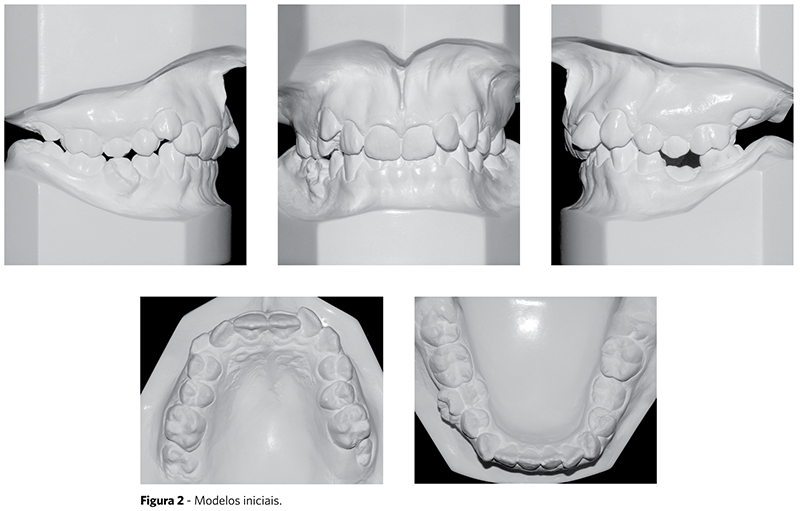

A paciente se encontrava em fase final da dentadura mista, com o dente 75 apresentando características clínicas de anquilose (Fig. 1). Na análise de modelos, foi possível observar a relação dentária de Classe II de Angle, divisão 2, ligeiramente assimétrica, com sobremordida e curva de Spee muito acentuadas. Observou-se, ainda, sobressaliência de 0,5mm e linha média inferior deslocada 2mm para a esquerda, além de apinhamento anterior superior e inferior (Fig. 2).